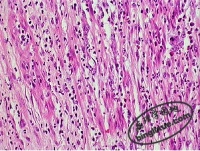

白喉的病变分为局部假膜性炎症及外毒素引起的毒血症两方面。白喉杆菌侵入咽部粘膜后即在粘膜表层组织中生长繁殖,一般不引起菌血症。白喉杆菌产生的外毒素为致病的主要因素,该毒素有A、B两个片段,B片段无直接的毒性,但当它与细胞表面受体结合,A片段即进入细胞内,从而对细胞发生直接致死作用。其病变表现为局部粘膜上皮细胞坏死,并逐渐扩大融合,同时可见局部粘膜血管扩张充血,大量纤维蛋白渗出。渗出的纤维蛋白与坏死细胞、白细胞和细菌凝结在一起,覆盖在破坏的粘膜表面,形成该病的特征性假膜。假膜一般为灰白色,有混合感染时呈黄色或污秽色,伴出血时呈黑色。假膜质地致密,开始薄,继之变厚,边缘较整齐,不易脱落,用力剥脱时可出血。假膜形成处及周围组织呈轻度充血肿胀。假膜可由扁桃体向咽峡、鼻、喉、气管、支气管等处扩展,鼻咽、气管处的假膜易于脱落造成呼吸窒息。假膜范围愈广泛,毒素吸收量愈大,中毒症状亦愈重。如毒素只吸附于细胞表面,可为抗毒素所中和,若已进入细胞内,则不能被抗毒素中和。

外毒素与各组织细胞结合后可引起全身性病变化。其中以心肌、末梢神经、肾上腺等较著。心肌细胞混浊肿胀,有脂肪变性、玻璃样及颗粒样变性,间质水肿、重者肌纤维可断裂、心肌坏死及单核细胞浸润,传导束可受累。神经病变多见于末梢神经,髓鞘常呈脂肪变性,神经轴索肿胀、断裂、感觉神经和运动神经均可受累,但经运动神经为主。麻痹多发生在眼、咽、喉部肌肉,也可发生于四肢。肾脏可呈混浊肿胀及肾小管上皮细胞脱落。肝细胞可呈脂肪变性,肝小叶呈中央坏死。